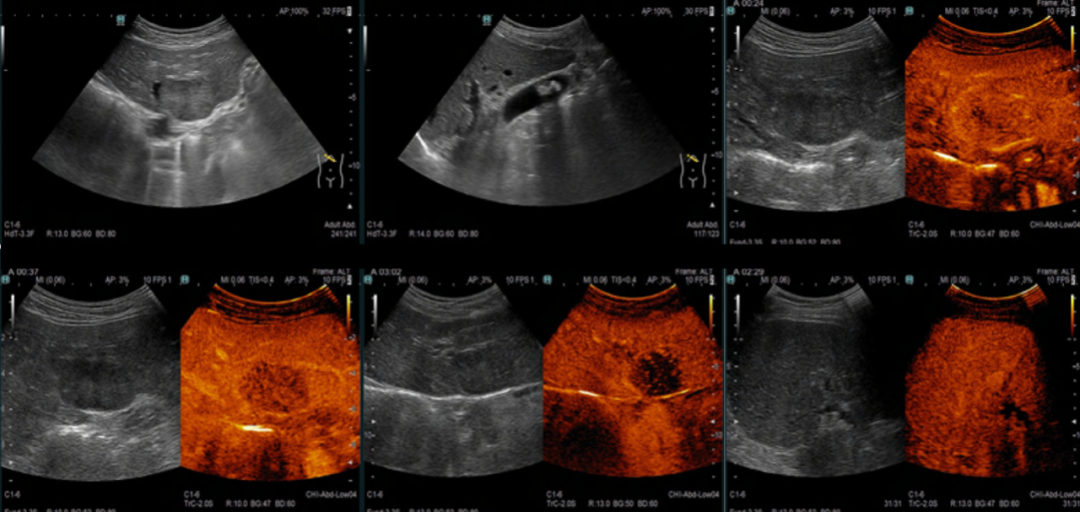

2020-10-26上腹部彩超+声学造影:肝左外叶实性结节,结合超声造影考虑Malignant(拟转移性病灶,CEUS LR- M 类)。

肝切面形态正常,肝内回声均匀,在肝左外叶可见1个肿块图像,大小约42*31mm,形态呈椭圆形,内部为低回声,内部回声分布均匀。CDFI:病灶内未见明显血流信号。超声造影:浅静脉团注1.2mL声诺维后动态观察并存储录像,肝左外叶病灶动脉期不均质稍低增强,门脉期早期、轻度廓清,延迟期病灶明显廓清,呈均匀低增强,似黑洞征。延迟期余肝扫查未见异常廓清病灶。

2程治疗后疗效评价:

肝左外叶实性结节,大小约30*20mm,形态呈椭圆形,内部为低回声,内部回声分布均匀。CDFI:病灶内未见明显血流信号。结合超声造影考虑Malignant(拟转移性病灶治疗后改变,病灶较化疗前检查明显缩小,超声造影显示病灶内大部分无活性,CEUS LR- Treated)。